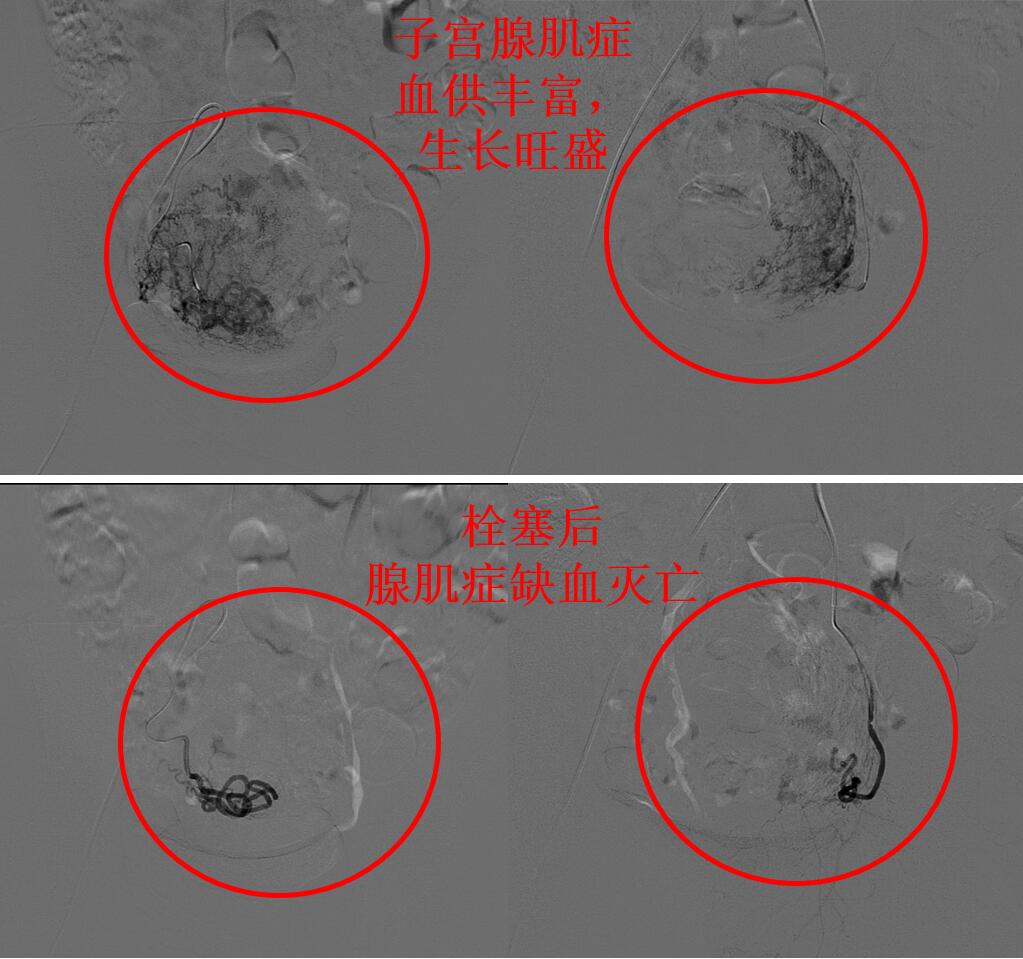

通过磁共振评估显示蓝护士的子宫腺肌症血供丰富,经大腿打针超选择栓塞子宫腺肌症的供血血管杀死腺肌症病灶会取得良好的疗效,则行子宫腺肌病介入超选择栓塞治疗(如下图)。

介入微创栓塞治疗后第2天,蓝护士即可下床步行活动。治疗后2个多月蓝护士来例假,无痛经,月经量明显减少,6天干净。3个月后复查磁共振显示:子宫腺肌症灭亡,子宫缩小(如下图)。